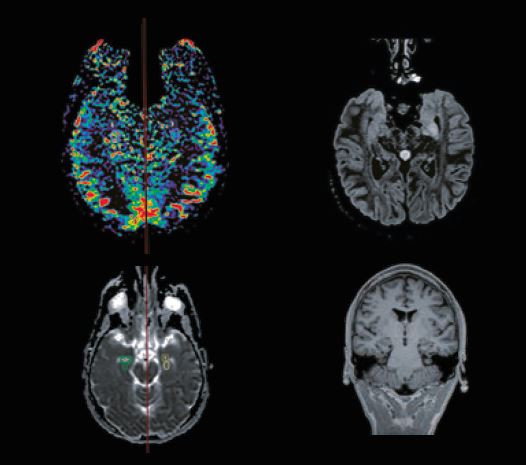

На рисунку 2 показано склероз лівого гіпокампу у пацієнта з лівосторонньою скроневою епілепсією.

Рис. 2 Склероз гіпокампу: зниження CBF (угорі ліворуч), гіперінтенсивне зображення склерозу на аксіальному FLAIR MPR (угорі праворуч), карта ADC (внизу ліворуч) і корональний MPRAGE MPR.

Зображення FLAIR показують гіперінтенсивний сигнал у лівому гіпокампі, а MPRAGE використовується для класифікації склерозу. ROI встановлюються як на нормальній зоні, так і на склерозі карт ADC і церебрального кровотоку. ASL показує ліву скроневу гіпоперфузію.